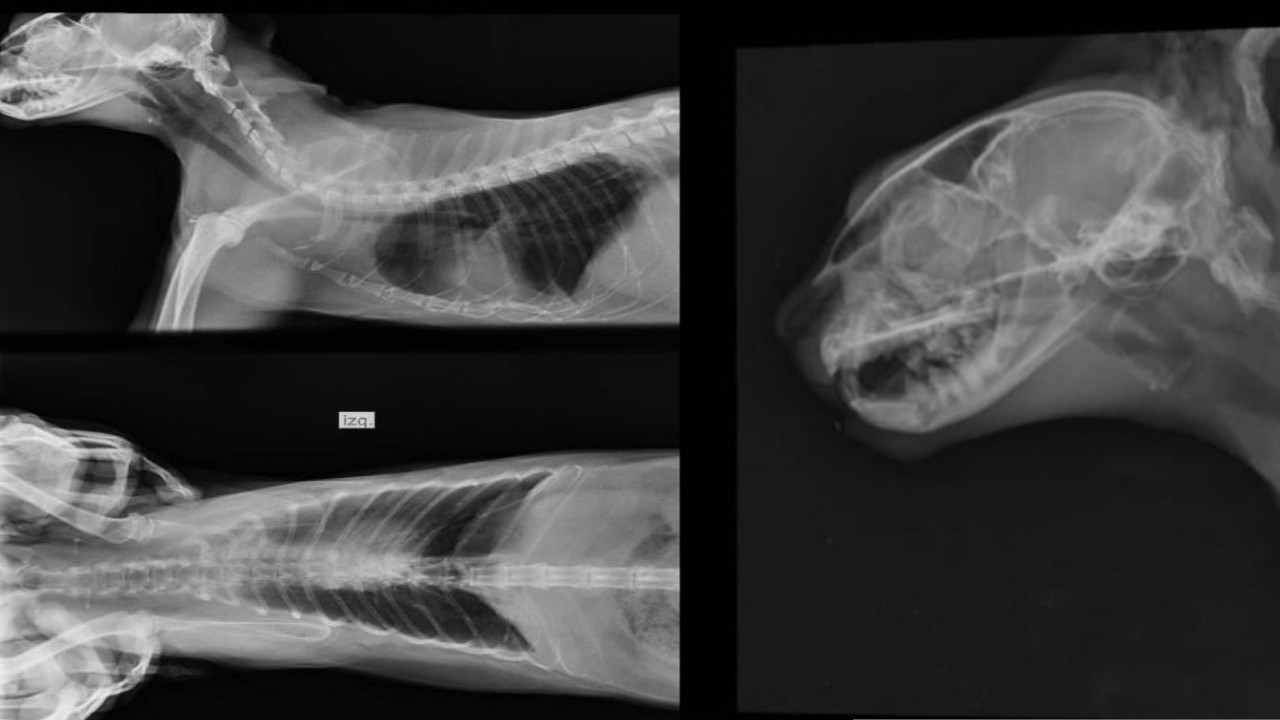

“Kiara” fue apuñalada

Los hechos ocurrieron el 14 de enero de 2020 en el corregimiento de San Juan de la China, en Ibagué.

“Kiara” estaba acompañando a su dueño mientras él limpiaba un cultivo de café y el hombre investigado pasó por el lugar, al parecer, diciendo que iba a matar a la perra porque mordía a otros animales.

Minutos después habría vuelto al lugar y atacado a la perra con un arma cortopunzante.

Afortunadamente después de 13 días de atención en un centro veterinario, “Kiara” se recuperó.